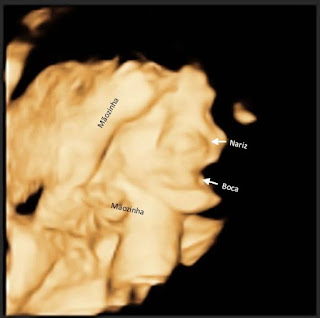

Fizemos a ultra e adivinha? Baby Boy não deixou ver o rostinho, de novo!! A imagem está melhor do que a anterior, mas só dá pra ver a boquinha e o nariz...

Agora é esperar pra ver ao vivo e à cores msm né...papai até falou de tentar fazer na próxima ultra, com 36 semanas, mas acho que é jogar R$ 50,00 no lixo...

Mas graças a Deus ele está perfeitinho, pesando 1.385 kg e medindo 38 cm...desses, 6 cm são só de pé! kkkk O coraçãozinho batendo a 153 bpm, coisa mais fofaa 😍😍